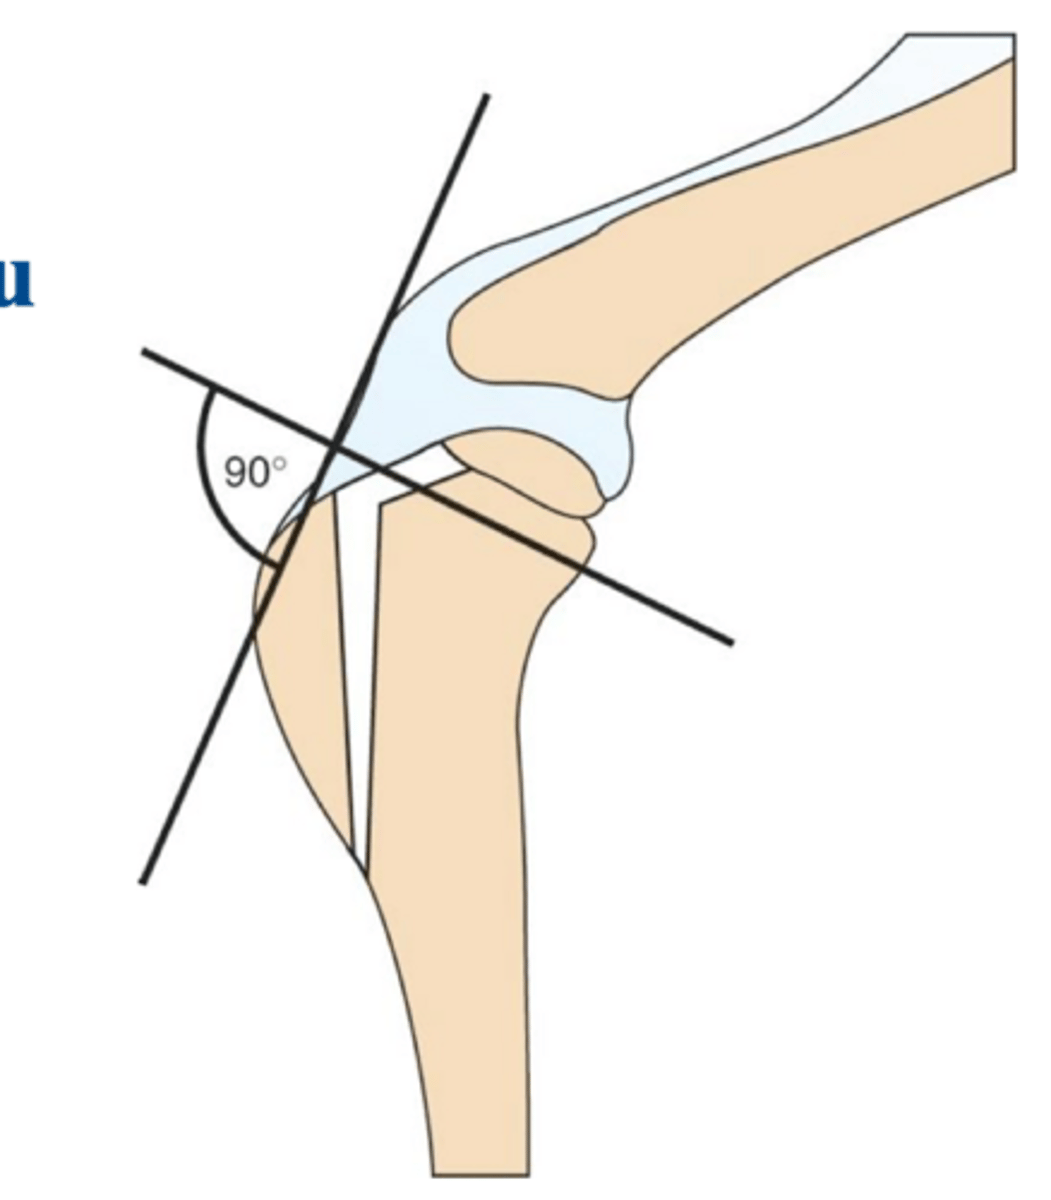

osteotomy of NWB portion of tibia to make tibial plateau 90 degrees to the patellar ligament to stabilize the stifle

general idea of the tibial tuberosity advancement (TTA) procedure **same general idea for TPLO**

1. place patellar lig. 90 degrees to slope of tibial plateau

2. advance insertion of tibial tuberosity in cranial direction

3. eliminate tibiofemoral shear and relieve function of CCL

biomechanics of the TTA procedure

post-op RADS of TTA

what is shown here